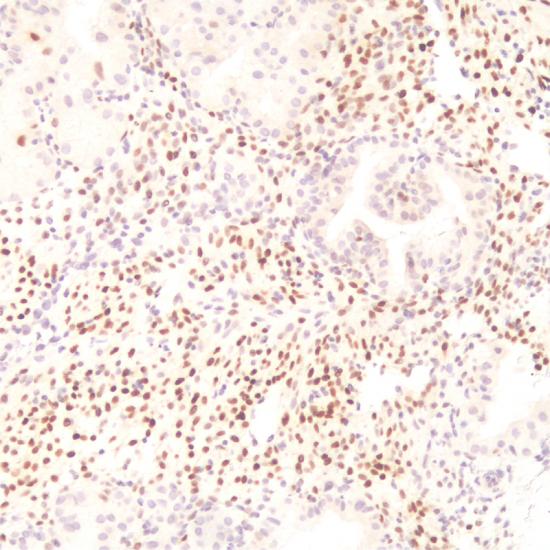

p57抗體試劑(免疫組織化學) 閩廈械備20180286號

• 陽性部位:

細胞核

• 陽性對照:

胎盤

p57是一種細胞周期依賴的激酶抑制劑和抑癌基因,定位于染色體11P15.5。在妊娠宮內膜中,蛻膜細胞p57表達陽性,但是分泌腺體中陰性。正常胎盤中,>30%滋養(yǎng)葉細胞、絨毛間質及絨毛中央滋養(yǎng)層細胞島細胞核表達該抗體,合體滋養(yǎng)層陰性。完全性葡萄胎均由父系DNA產(chǎn)生,p57不表達;部分性葡萄胎有父母雙方DNA,表達p57,故該抗體可以用于研究完全性及部分性葡萄胎。